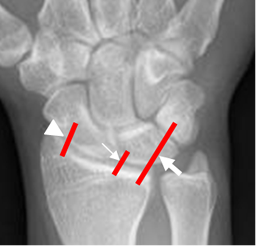

Fig 3. Ligamentos extrínsecos posteriores.

Rx AP. Ligamento radiocarpal con sus componentes radioescafoideo (Punta de flecha), radiolunado (Flecha delgada) y radiopiramidal (Flecha gruesa).